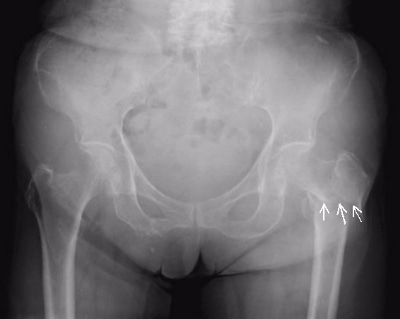

大腿骨の内側顆と外側顆の近位で折れた大腿骨骨折を大腿骨顆上骨折といいます。